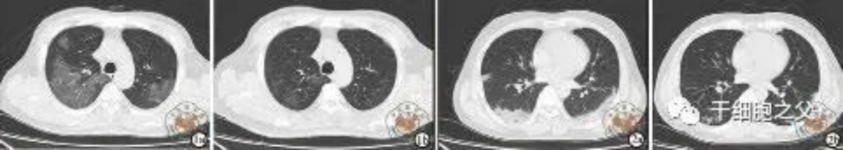

与安慰剂组相比,人脐带间充质干细胞修复组全肺病变体积改善了10.8%,并且人脐带间充质干细胞修复组在每一个随访节点都显示出固体组分病变体积比例减少。此外,人脐带间充质干细胞组有17.9%的患者在12个月时CT图像变为正常,而安慰剂组没有。

研究结果:细胞输注后,炎症指标改善,复查胸部CT提示双肺病灶较前吸收,呼吸道症状改善,新型冠状病毒核酸检测连续2次阴性,治愈出院。